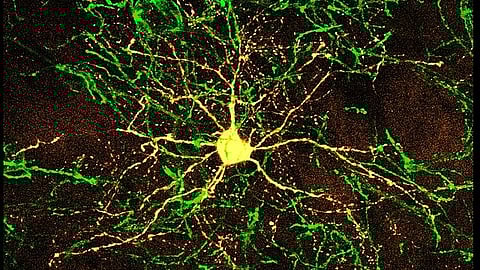

In the present study, the researchers focused on the hippocampal interneurons in a specific region, called the hilus of the dentate gyrus, that are characterized by their expression of somatostatin. This hormone has the ability to counteract the effects of growth hormones elsewhere in the body.

The researchers decreased the numbers of somatostatin-positive interneurons in the hippocampus of mice by using a toxin. They injected this toxin into the dentate hilus, so that the toxin would only be expressed in the somatostatin-positive interneurons, killing approximately 50% of these cells. Starting 3 weeks later, they conducted behavioral studies to test the learning abilities and memory of the mice.

In addition to determining the status of microglia, the team measured a protein called brain-derived neurotrophic factor, which is active in the hippocampus and plays a role in long-term memory. They found that there were lower BDNF levels in the hippocampal tissue of the toxin-injected mice. Furthermore, the researchers also found that these mice had fewer hippocampal dendritic spines, which are critical for learning and memory.